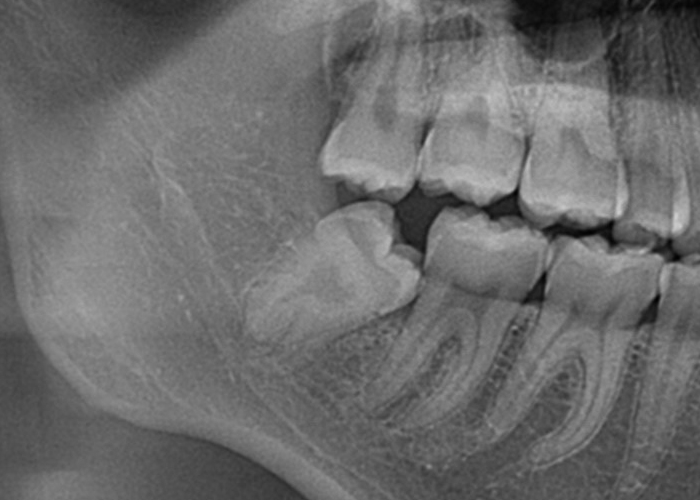

完全埋伏智歯(歯茎に完全に埋まっている)

完全埋伏とは、親知らずが完全に歯肉の下に完全に埋まっている状態を指します。

この場合、親知らずは通常、レントゲンやCTスキャンなどの画像検査でのみ確認できます。

完全埋伏の親知らずは、周囲の組織に直接的な問題を引き起こさない場合もありますが、将来的に問題を引き起こす可能性があります。

そのため、定期的な口腔検診や画像検査が重要です。

骨性完全埋伏智歯(骨に完全に埋まっている)

この場合も親知らずは通常、レントゲンやCTスキャンなどの画像検査でのみ確認できます。

もしこのような歯が抜歯が必要となった場合は近隣口腔外科への紹介をする場合があります。